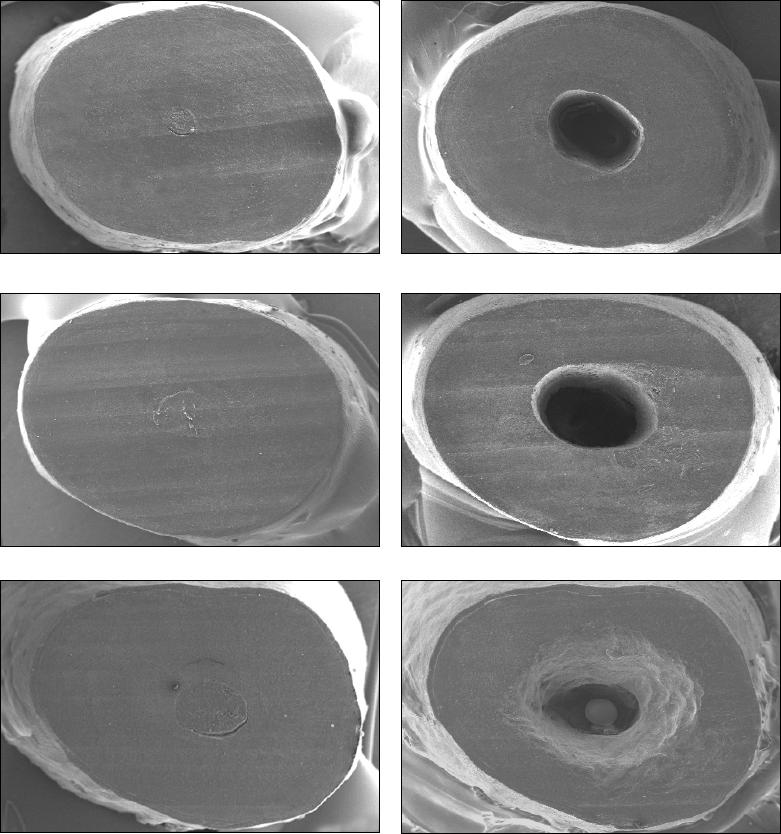

As fotomicrografias obtidas foram examinadas para avaliar a qualidade da

superfície radicular (20x), a presença de trincas (100x e 200x) e a adaptação da

guta-percha com as paredes do canal radicular (50x).

A qualidade da superfície radicular foi analisada de acordo com os seguintes

escores adaptado de Morgan, Marshall

24

(1998): 1 – superfície essencialmente de

aspecto vítreo, sem a presença de marcas de instrumento; 2 – superfície

essencialmente lisa, mas com discretas marcas de instrumento; 3 – superfície

visivelmente estriada, revelando nítidas marcas de instrumento; e 4 – superfície

irregular, com marcas grosseiras de instrumento de profundidade exagerada (Figura

1).

A adaptação da guta-percha com as paredes do canal radicular foi avaliada

de acordo com os escores: 1 – guta-percha bem adaptada às paredes do canal

radicular; 2 – guta-percha recobrindo as bordas das paredes do canal radicular; 3 –

presença de lacunas de até 21,45µm ocasionados pelo deslocamento da obturação

durante a apicectomia; e 4 - presença de lacunas acima de 21,45µm ocasionados

pelo deslocamento da obturação durante a apicectomia (Figura 2). O valor de

21,45µm correspondeu à mediana dos valores encontrados nos espécimes que

apresentavam essas falhas. Todas as mensurações foram realizadas com o auxílio

de um programa de análise de imagens (Image Tool for Windows version 3.00,

UTHSC, SA, USA).